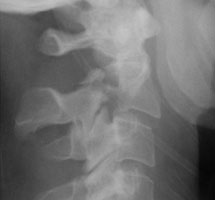

The Hangman's fracture consists of bilateral pedicle or pars fractures involving the C2 vertebral body. Associated with this fracture is anterior subluxation or dislocation of the C2 vertebral body. It results from a severe extension injury such as from an automobile accident where the face forcibly strikes the dashboard or from hanging.

- Click on the image for a larger versionALateral radiograph of the cervical spine. This shows bilateral pars fractures at the C2 level.